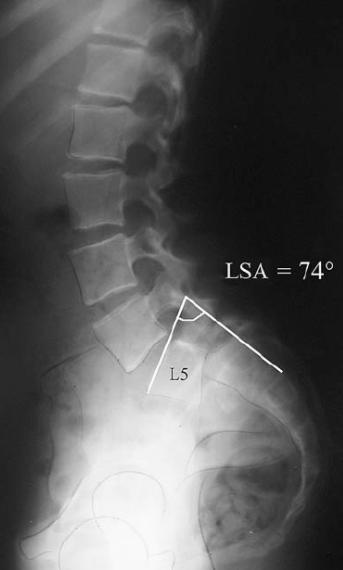

Ângulo de Boxall: como é? para que serve

Ângulo entre linha perpendicular cortical posterior sacro e linha paralela superfície articular inferior ou superior L5

>55º tem mais chance de progressão espondilistese